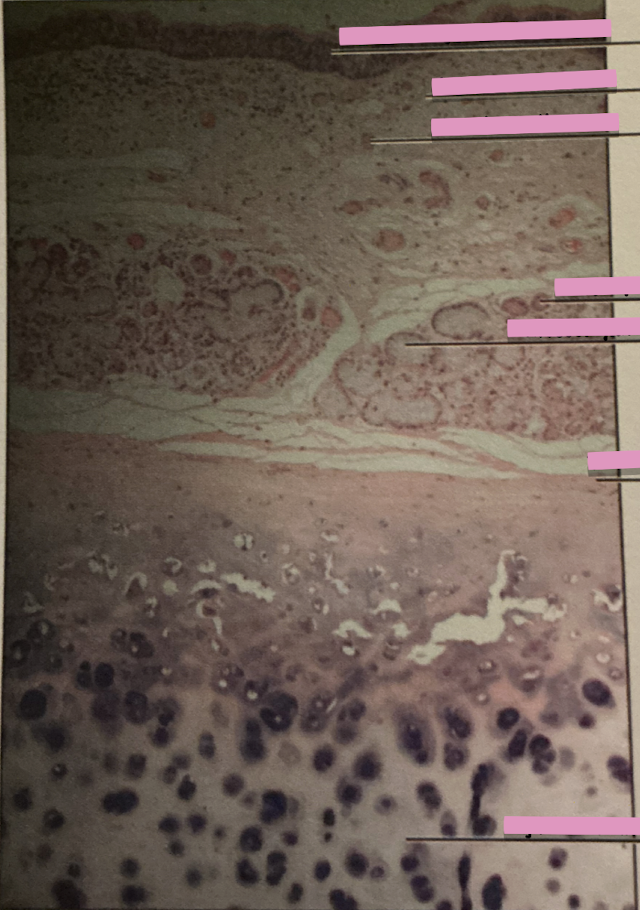

lip at 40x

lip at 100x

labial glands

seromucous salivary glands

taste buds at 40x

taste buds at 400x

taste buds

clusters of encapsulated gustatory receptor cells onf surface of tongue

papillae

concentrated on surface of peg-like projections called ______

gustatory epithelial cells

receptor cells for taste

basal epithelial cells

stem cells dividing to produce new gustatory epithelial cells

dentin

what do odontoblasts make?

pulp

in tooth - soft inner core w/ blood and nerve supply

tooth